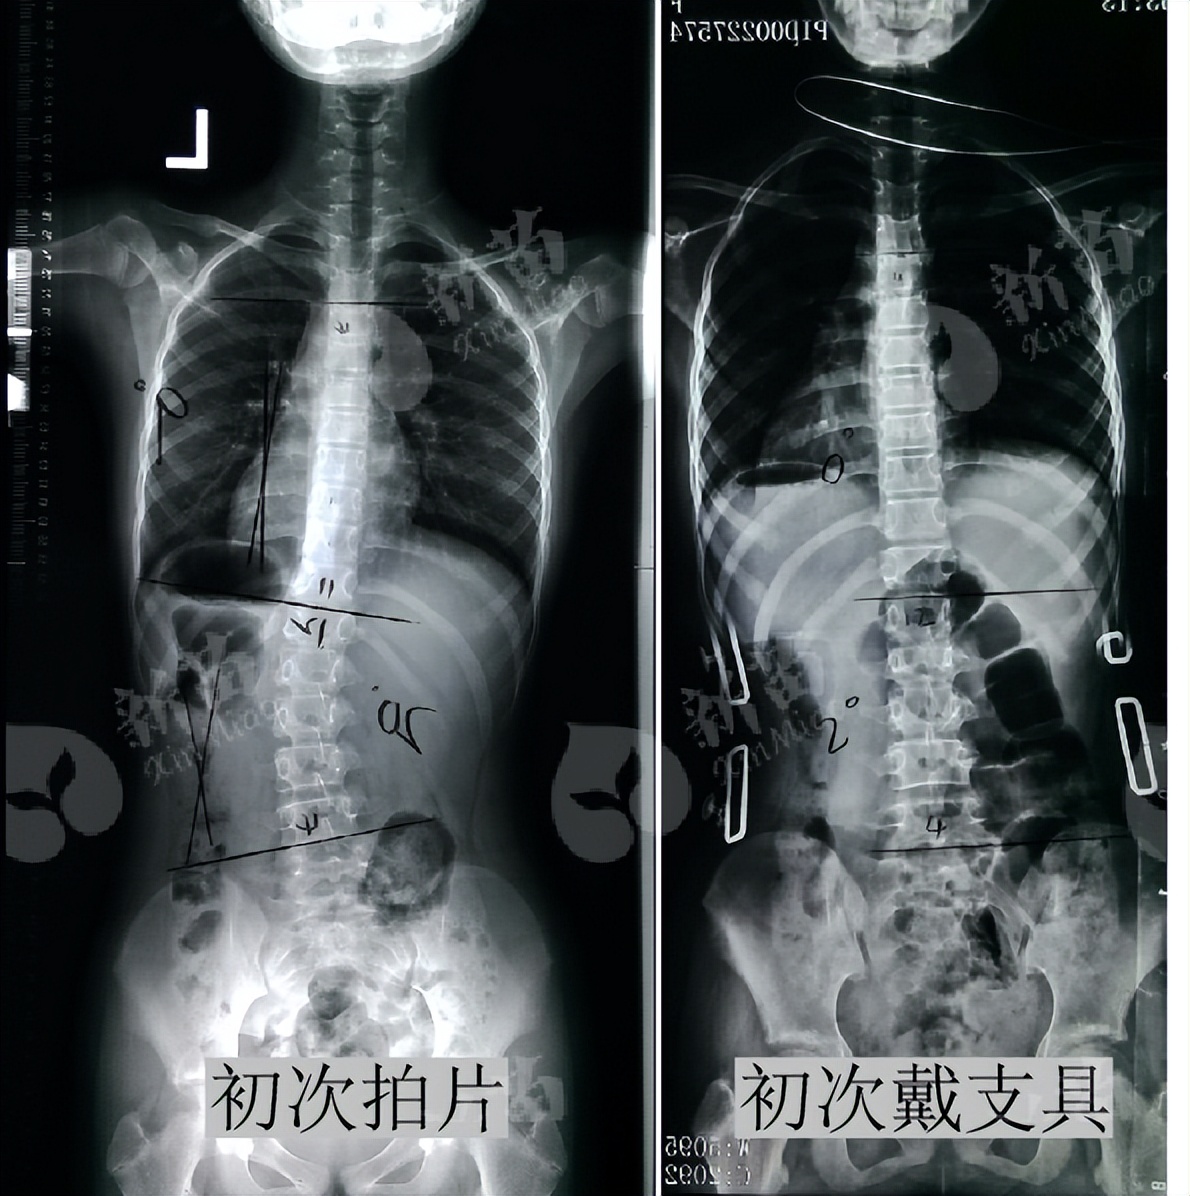

小乔(化名)12岁时,学校筛查出疑似脊柱侧弯。随后家长带着孩子去医院检查, 确诊脊柱侧弯,腰椎向左弯曲20°,伴有椎体旋转、颈椎变直、骨盆倾斜等问题 。

2021年11月复诊,小乔 脱下支具2天 后拍摄全脊柱X光片,脊柱侧弯角度腰弯 20°降至4° 。背部外观上,两侧肩胛骨也较以前对称,两侧腰部基本对称。

小乔是12岁拍片发现的脊柱侧弯,这个年阶段的孩子仍处于 生长发育较快的时期 ,她的X光片显示侧弯20°伴椎体旋转,针对小乔的情况,结合病情后我们设定了针对性的医学形体训练和支具治疗方案。

首先,小乔发现侧弯时是12岁,X光片显示 Risser征0级 ,正常情况下, 青少年Risser征在3级以内都是脊柱侧弯矫正的黄金期 ;加上小乔柔韧性好,通过以支具矫正与形体训练相结合的有效治疗,小乔的脊柱基本回直。

(首次佩戴支具,侧弯T4-T11右侧凸矫正至0°,T12-L4左侧凸矫正至2°)